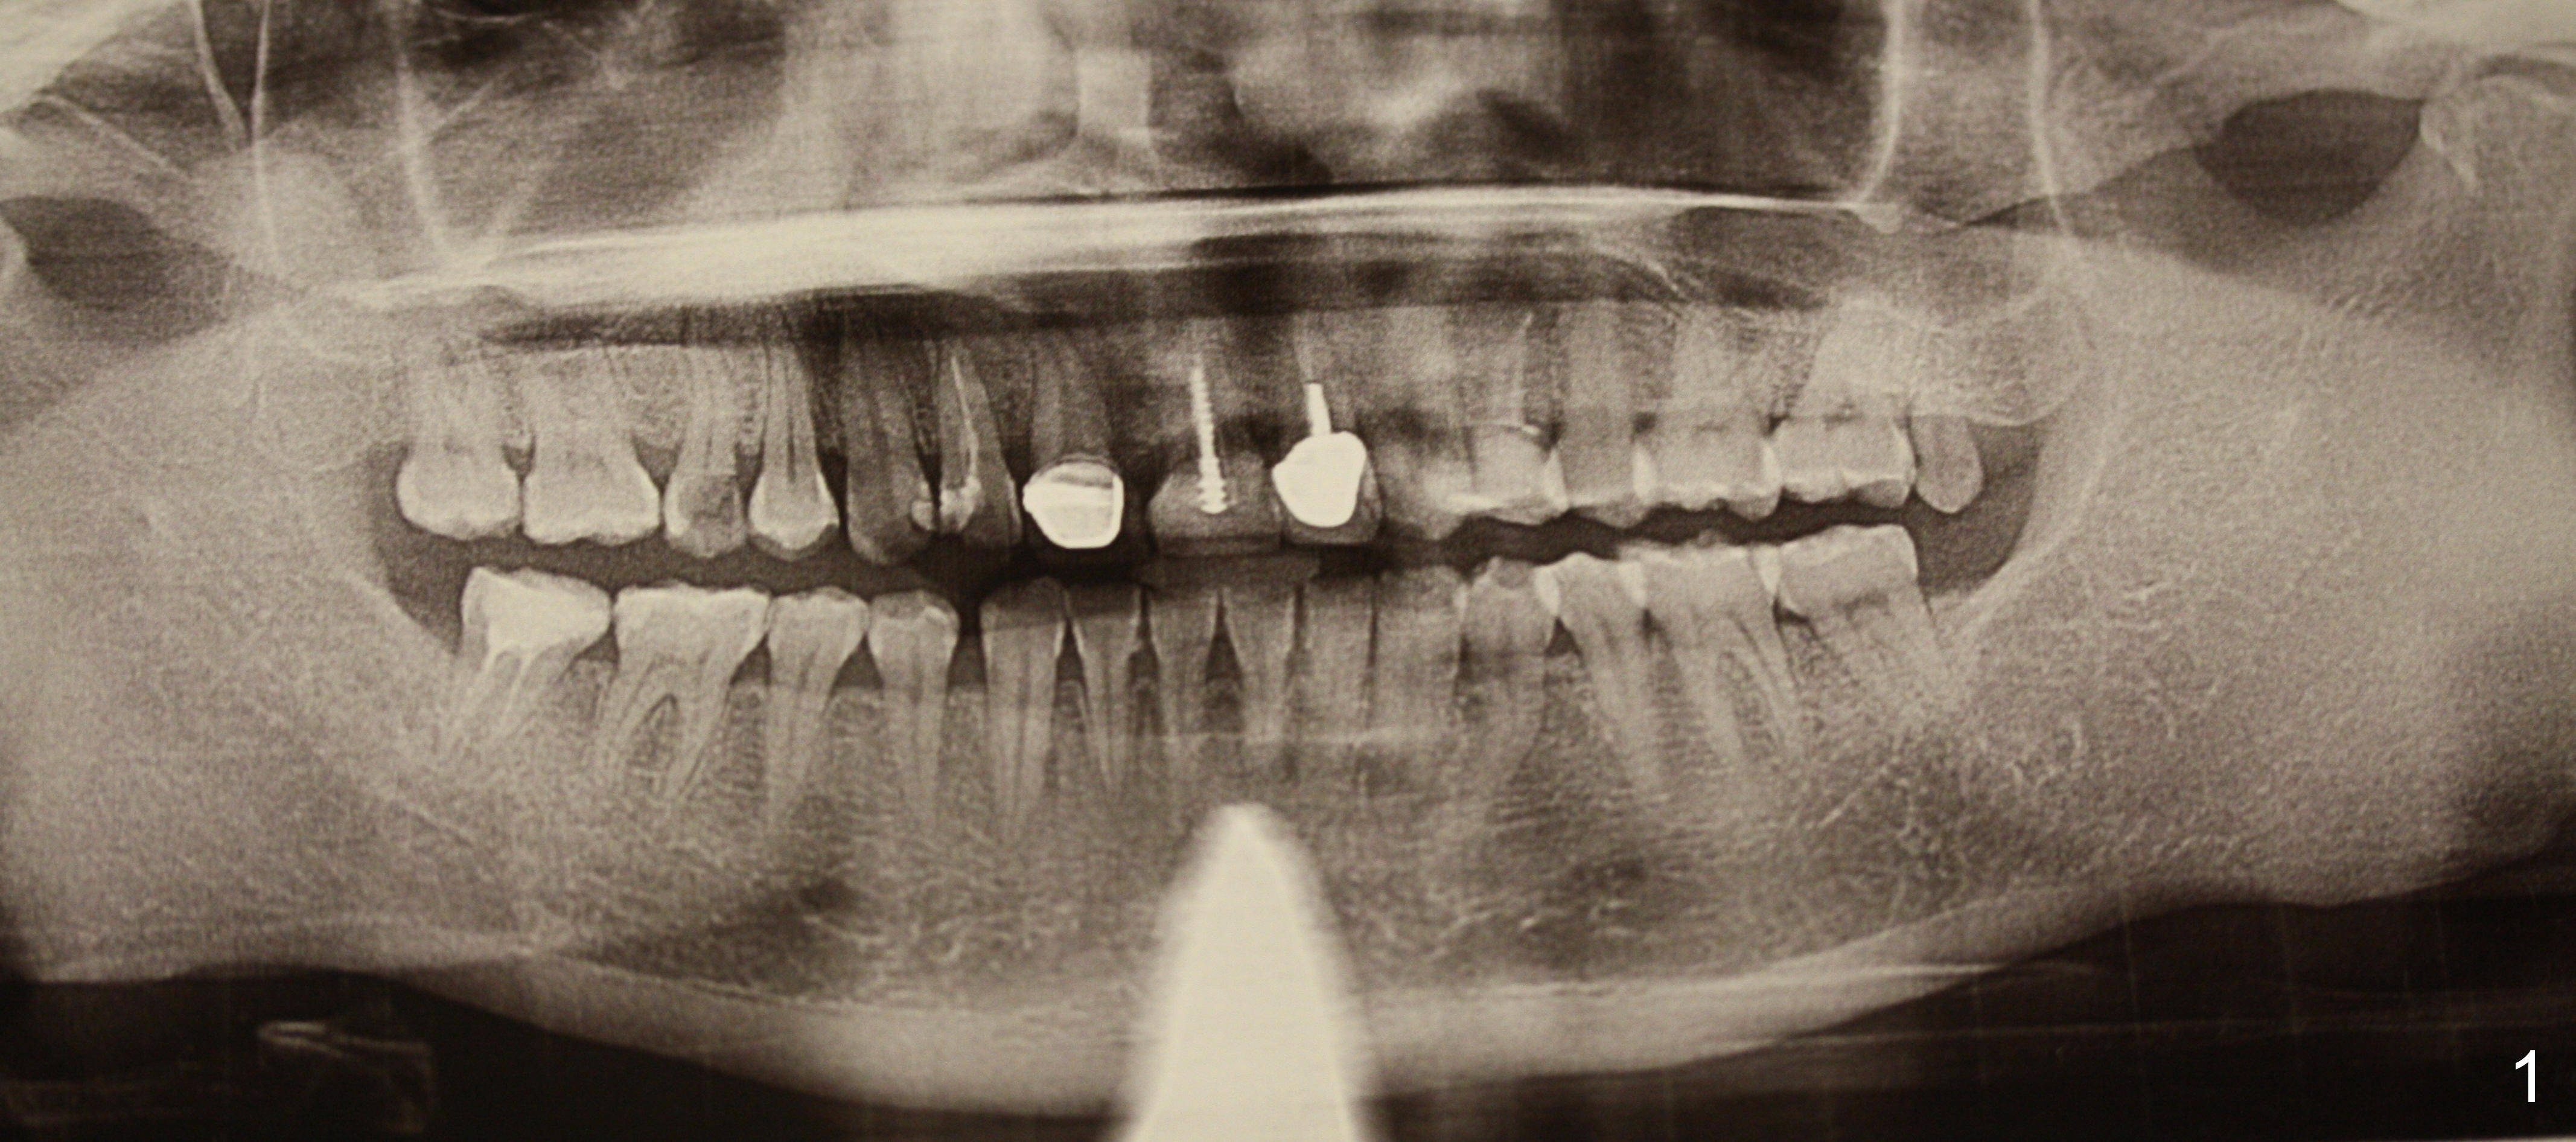

A 40-year-old lady has multiple restorations (Fig.1). Two of them require implants (#4 (Fig.2, severe caries) and #8 (Fig.3, root fracture). The root of #4 is long and curved (Fig.2). It may present a challenge to extraction, but not implant placement. The narrow and long root is favorable to primary stability. A 2 mm pilot drill is used to initiate osteotomy in the palatal wall of the socket, followed by 2.5 and 3 mm reamers at 17 mm (gingival level). If the bone is soft, the depth for the 3 mm reamer will be reduced to 14 mm. A 4.5x20 mm Tatum tapered tap will be used at 17 mm deep to test stability.

If the stability is good, a bone-level implant will be placed. How long is the implant? Why do we not use a tap from the bone-level implant kit?